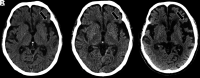

FIG 2.

Coronal T1-weighted MR imaging (A), axial T1-weighted MR imaging (B), and sagittal T1-weighted MR imaging (C) in a right-handed individual with impaired repetition of phrases demonstrate asymmetric widening of the left Sylvian fissure with left posterior peri-Sylvian and temporoparietal atrophy (white arrows, A–C), suspicious for lvPPA.